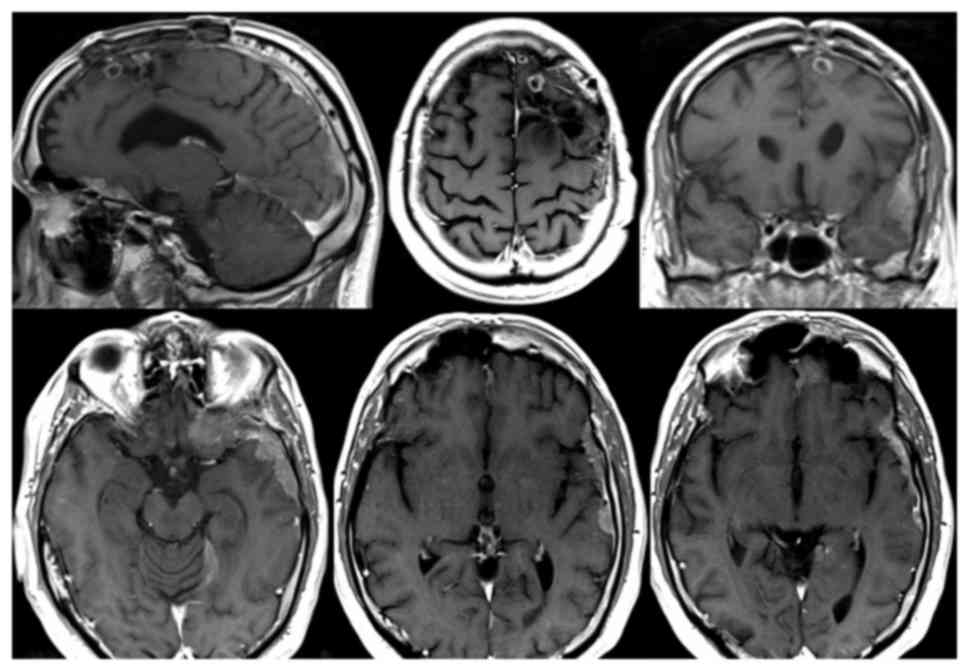

At the end of September, adjuvant chemotherapy was adopted according to the scheme: Carboplatin AUC5 IV day 1 every 21 days and Etoposide 100 mg/mq IV day 1–3 every 21 days. After 2 cycles of chemotherapy, which the patient well-tolerated, a control brain MRI was performed and documented a significant regression of the diffuse leptomeningeal thickening with maximum residual of 4–5 mm (Fig. 5). It also showed a stability of left frontomesial nodules and of the lesion of the corpus callosum. Patient clinical condition and KPS were stable.

Figure 5.

Contrast-enhanced brain MRI at postoperative month 9. Following 2 cycles of carboplatin and etoposide chemotherapy, brain MRI revealed stability of the left frontal paracentimetric nodule and a marked reduction of the frontotemporal leptomeningeal ‘en plaque’ localization. MRI, magnetic resonance imaging.